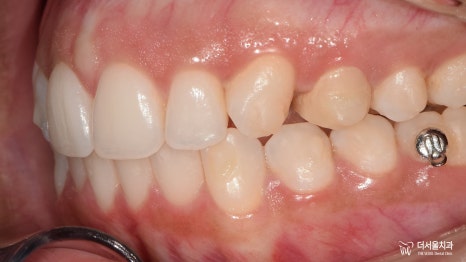

마지막으로 안모 변화를 비교해 보면

훨씬 자연스럽고 안정적으로 물리는

전, 후 안모 사진을 확인할 수 있네요.